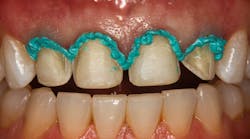

A 68-year-old patient presented with the upper right first premolar with occlusal amalgam and two distal marginal ridge fractures and discoloration under the mesial marginal ridge (figure 1). He previously had an extraction due to a fracture on his lower arch and wanted to treat the upper first premolar proactively. The existing occlusal amalgam was removed under rubber dam isolation. Caries were visualized clinically, and cracks were visualized with transillumination under both marginal ridges (figure 2). The premolar was prepared using a nonretentive cavity preparation design to allow the resin to flow in, out, and around the tooth (figure 3). Particle abrasion with 27 microns at 40 psi (PrepStart, Danville Products) was completed for microretention and biofilm removal before matrices, phosphoric acid etch (figure 4), and adhesive were placed.